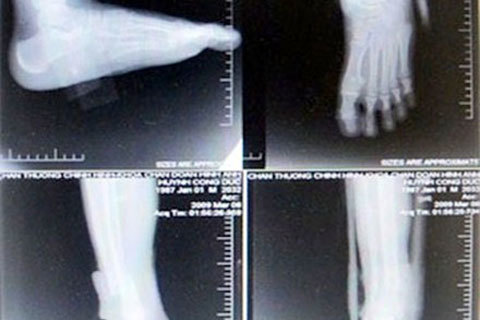

Bằng thủ đoạn cắt xén, tráo đổi và ghép phim X-quang, nhiều năm nay, một số bác sĩ ở bệnh viện Chấn thương chỉnh hình TP.HCM đã “móc túi” nhiều tỷ đồng từ hàng vạn bệnh nhân.

Theo thông tin trên báo Tiền phong, nhóm bác sĩ ở BV Chấn thương chỉnh hình đã phát hiện một số bác sĩ ở khoa Chẩn đoán hình ảnh của bệnh viện này đã “ăn phim” từ năm 2007, kéo dài đến năm 2012.

Một bệnh nhân chụp cổ chân ở mọi tư thế bị ghép phim. Ảnh: Lao động |

Theo bác sĩ V.B.L, khoa Chẩn đoán hình ảnh, các bác sĩ Hồ Văn Thạnh, Trưởng khoa Chẩn đoán hình ảnh cùng ông Bùi Văn Hải, Phó khoa và kỹ thuật viên trưởng Bùi Bảo Vinh đã chỉ đạo các nhân viên dưới quyền ghép, cắt, đổi, gian lận trong việc nhập và xuất phim cho bệnh nhân để hưởng lợi hàng tỉ đồng.

Thủ đoạn để ba người này “móc túi” người bệnh là khi bệnh nhân được chỉ định chụp X-quang loại phim A kích thước 35 x 43cm, kỹ thuật viên cắt xén một nửa khi chụp, chỉ còn kích thước 35 x 21,5cm. Ngoài việc xén, kỹ thuật viên dùng thêm thủ thuật tráo đổi phim, bằng cách sử dụng hai loại phim A giá 42.000 đồng/tấm thay cho phim B có kích thước 26 x 36cm giá 23.000 đồng/tấm.

Đơn cử bệnh nhân được chỉ định chụp X-quang phim A, kỹ thuật viên phù phép thành phim B, trong khi bệnh nhân được chỉ định chụp hai phim B thì kỹ thuật viên chụp ghép trên một phim A.

Một bác sĩ nói, gian lận bằng cách đánh tráo phim X-quang diễn ra thường xuyên. Ví dụ, bác sĩ thu tiền của bệnh nhân với giá phim loại A nhưng lại chụp cho họ với phim loại B có giá rẻ hơn. Trong khi đó, thủ thuật lắp ghép phim diễn ra còn dễ dàng hơn khi người bệnh đóng tiền chụp cho hai phim, nhưng khoa chụp ghép nhiều bộ phận cơ thể cần chụp trên 1 phim, rồi cắt nhỏ phim ra đưa cho bệnh nhân.

Theo một bác sĩ, việc tráo, cắt xén và ghép phim này không gây thất thoát tiền phim cho bệnh viện, nhưng rõ ràng bệnh nhân đã bị móc túi một cách không thương tiếc.